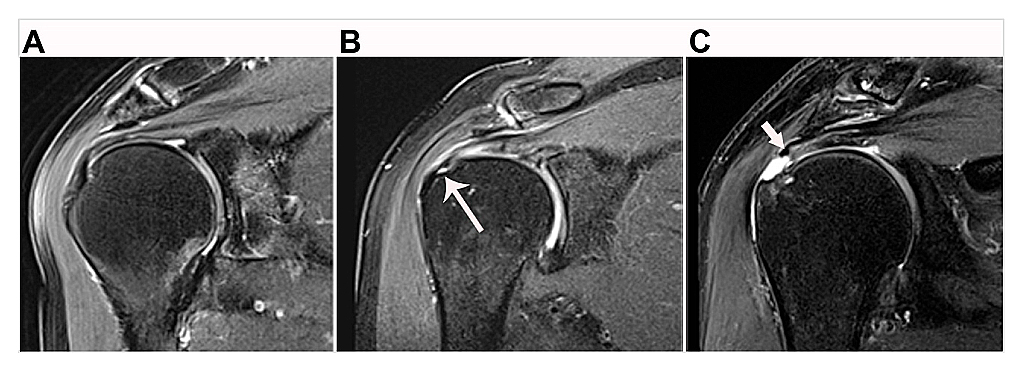

Imaging is central for establishing the clinical diagnosis and prognosis for patients presenting with either traumatic acute-onset shoulder dysfunction or non-traumatic shoulder disorders which are not self-limited [22,44,45]. Magnetic resonance imaging (MRI) is the leading imaging modality in the United States to provide definitive imaging evaluation of patients with symptomatic shoulder dysfunction and is a valid and reliable method for diagnosing and characterizing the pattern of RC tear (Figure 1) [20,42,46–48]. MRI also provides concurrent prognostic information about the degree of intramuscular fatty infiltration associated with RC tear, a critical factor that influences orthopaedic surgeons’ clinical decision-making regarding patients’ eligibility to receive RC repair (RCR) surgery (Figure 2) [20,42,46–50]. RC tear is associated with structural changes in the corresponding muscle belly related to intramuscular proliferation of adipose cells and inflammation, fibrosis and apoptosis of myofibers leading to global muscle atrophy and dysfunction [51–53]. Animal and human models of RC tear show that intramuscular fatty infiltration is inversely related to muscular contractile force at the rotator cuff and does not improve after RCR surgery [20,51,54]. During initial steps of pre-operative evaluation, imaging metrics of RC muscle quality are critical, as advanced RC intramuscular fatty infiltration is a relative contraindication to RCR surgery and is associated with poor postsurgical outcomes [46,48–50].

FIGURE 1

Figure 1. Examples of rotator cuff tendon classification on magnetic resonance imaging. (A) Supraspinatus tendon shows no sign of tear. (B) Partial-thickness tear of the supraspinatus tendon at its greater tuberosity humeral footprint (long arrow). (C) Full-thickness tear of the supraspinatus tendon with medial retraction of the tendon edge (short arrow) away from the greater tuberosity humeral footprint.